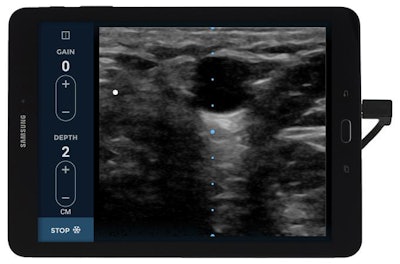

EchoNous Vein addresses the problem with ultrasound-based technology that scans at depths of 1 cm to 5 cm to quickly visualize both superficial and deeper veins. The scanner operates with simple two-button controls, and it includes settings that are optimized for children and adults.

Product testing has shown that the scanner's frequency profile and optimized gain and depth presets are particularly helpful to healthcare personnel for evaluating the veins of pediatric patients, who traditionally are a challenging patient population for IV insertion, according to the company.